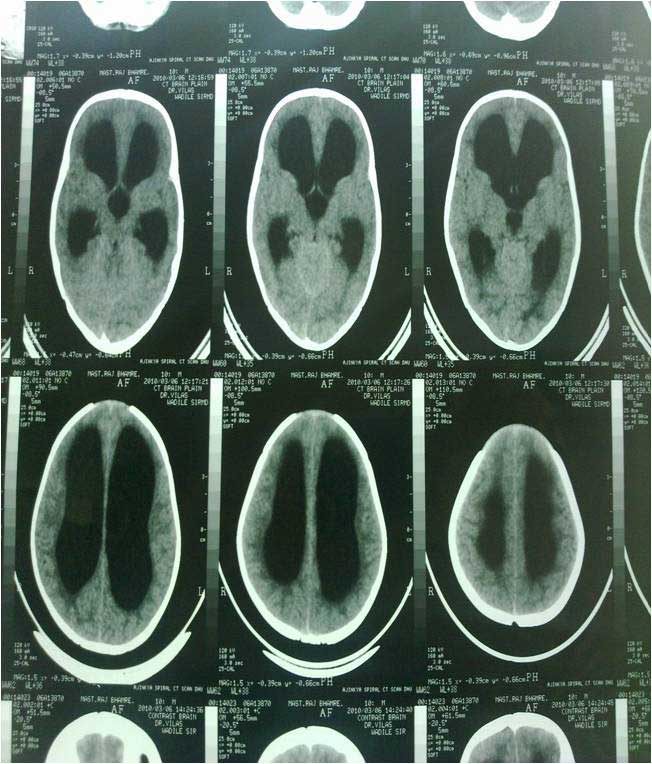

PRE OP CT 2

PRE OP CT